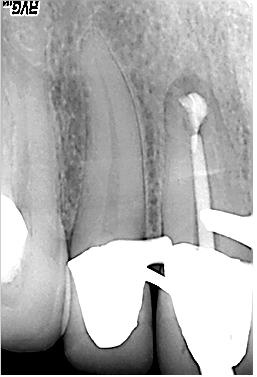

Masterpoinaufnahme

Masterpoinaufnahme. Mesial konnte keine „Patency“, das bewußte offenhalten des foramen apicale, hergestellt werden. Das distale Kanalsystem konnte gängig gemacht werden

WF-Kontrolle

Erste WF-Kontrolle. Das „Down Pack“, der apikale Anteil der thermoplastischen Wurzelfüllung des distalen Kanalsystems wird separat röntgenologisch überprüft